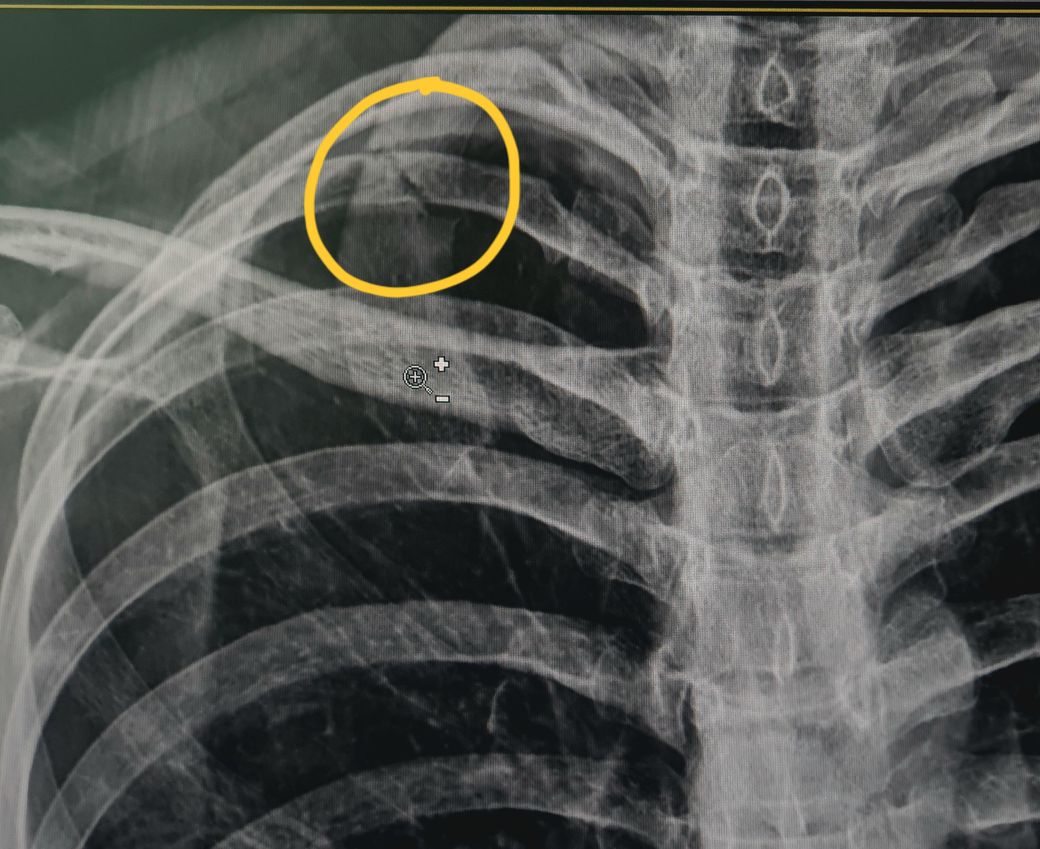

이 정도 갈비뼈 골절은 심한 편인가요?

최근 1번 갈비뼈가 골절됐습니다.

통증은 진통제 먹을정도는 아닌 미세하고 숨 크게 쉴 때나 웃을 때, 팔 들어 올릴 때 아픕니다.

이 부위(갈비뼈 1번)에 골절은 드물게 나타나는데, 이쪽은 혈관과 신경이 많이 지나가는 곳이기 때문에 여기 골절은 위험한 부위입니다.

갈비뼈 골절 관련해서 질문을 주셨는데 현재 1번 갈비뼈 골절이 된것으로 확인이 되며 진통제 없이도 참을 수 있을 정도 이긴 하지만 깊은 호흡이나 웃을때 팔을 들 때 통증이 있고 엑스레이상 명확하게 골절 부위가 관찰 되고 있는 것을 보았을때 골절이 비교적 경미한 상태로 보이며 안정적인 단일 골절로 확인이 됩니다.